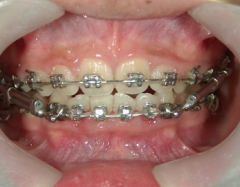

矯正歯科 治療前矯正歯科 治療前

矯正歯科 治療前 左右上下4番  計4本抜歯